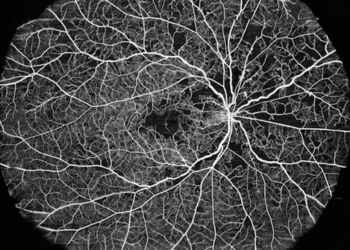

OCTA montage captured with VG-200I

Widefield Documentation

OCTA montage and optional UWF lens support help document larger retinal areas more efficiently.

• 23.5 × 17.5 mm OCTA montage

• Up to 200° with UWF lens